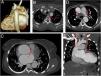

A 21-year-old female patient was admitted to our clinic with complaint of dyspnea. The computer tomography (CT) angiography showed aberrant right subclavian artery and aortic coarctation coexistence (Fig. 1A). Coarctation segment was seen on distal of arcus aorta just after to the originated of the left subclavian artery. There was also an aberrant right subclavian artery originated from the aortic coarctation segment (Fig. 1B). The aberrant subclavian artery was going to the right upper extremity following through to posterior of the esophagus. In addition to that, there was no the left main coronary artery. CT scans revealed the circumflex artery and left descending coronary artery originating from aorta directly (Fig. 1C). The patient had bicuspid aortic valve. There was also a double superior vena cava and an ascending aortic aneurysm (Fig. 1D and E). There were no abnormalities in bronchial distribution. The aortic coarctation segment was treated by stenting.

Posterior view 3D volume rendering CT angiography image (A) and axial CT scan in mediastinal window (B) show a coexistence of the aberrant right subclavian artery (long arrow) and aortic coarctation. The aberrant right subclavian artery originates from the aortic coarctation segment. Axial CT scan (C) reveals the circumflex artery (dashed arrow) and left descending coronary artery (short arrow) originating from aorta directly. Axial (D) and coronal (E) CT angiography scans show a double superior vena cava anomaly (frames). All CT scans also reveal cardiomegaly and ascending aortic aneurysm.